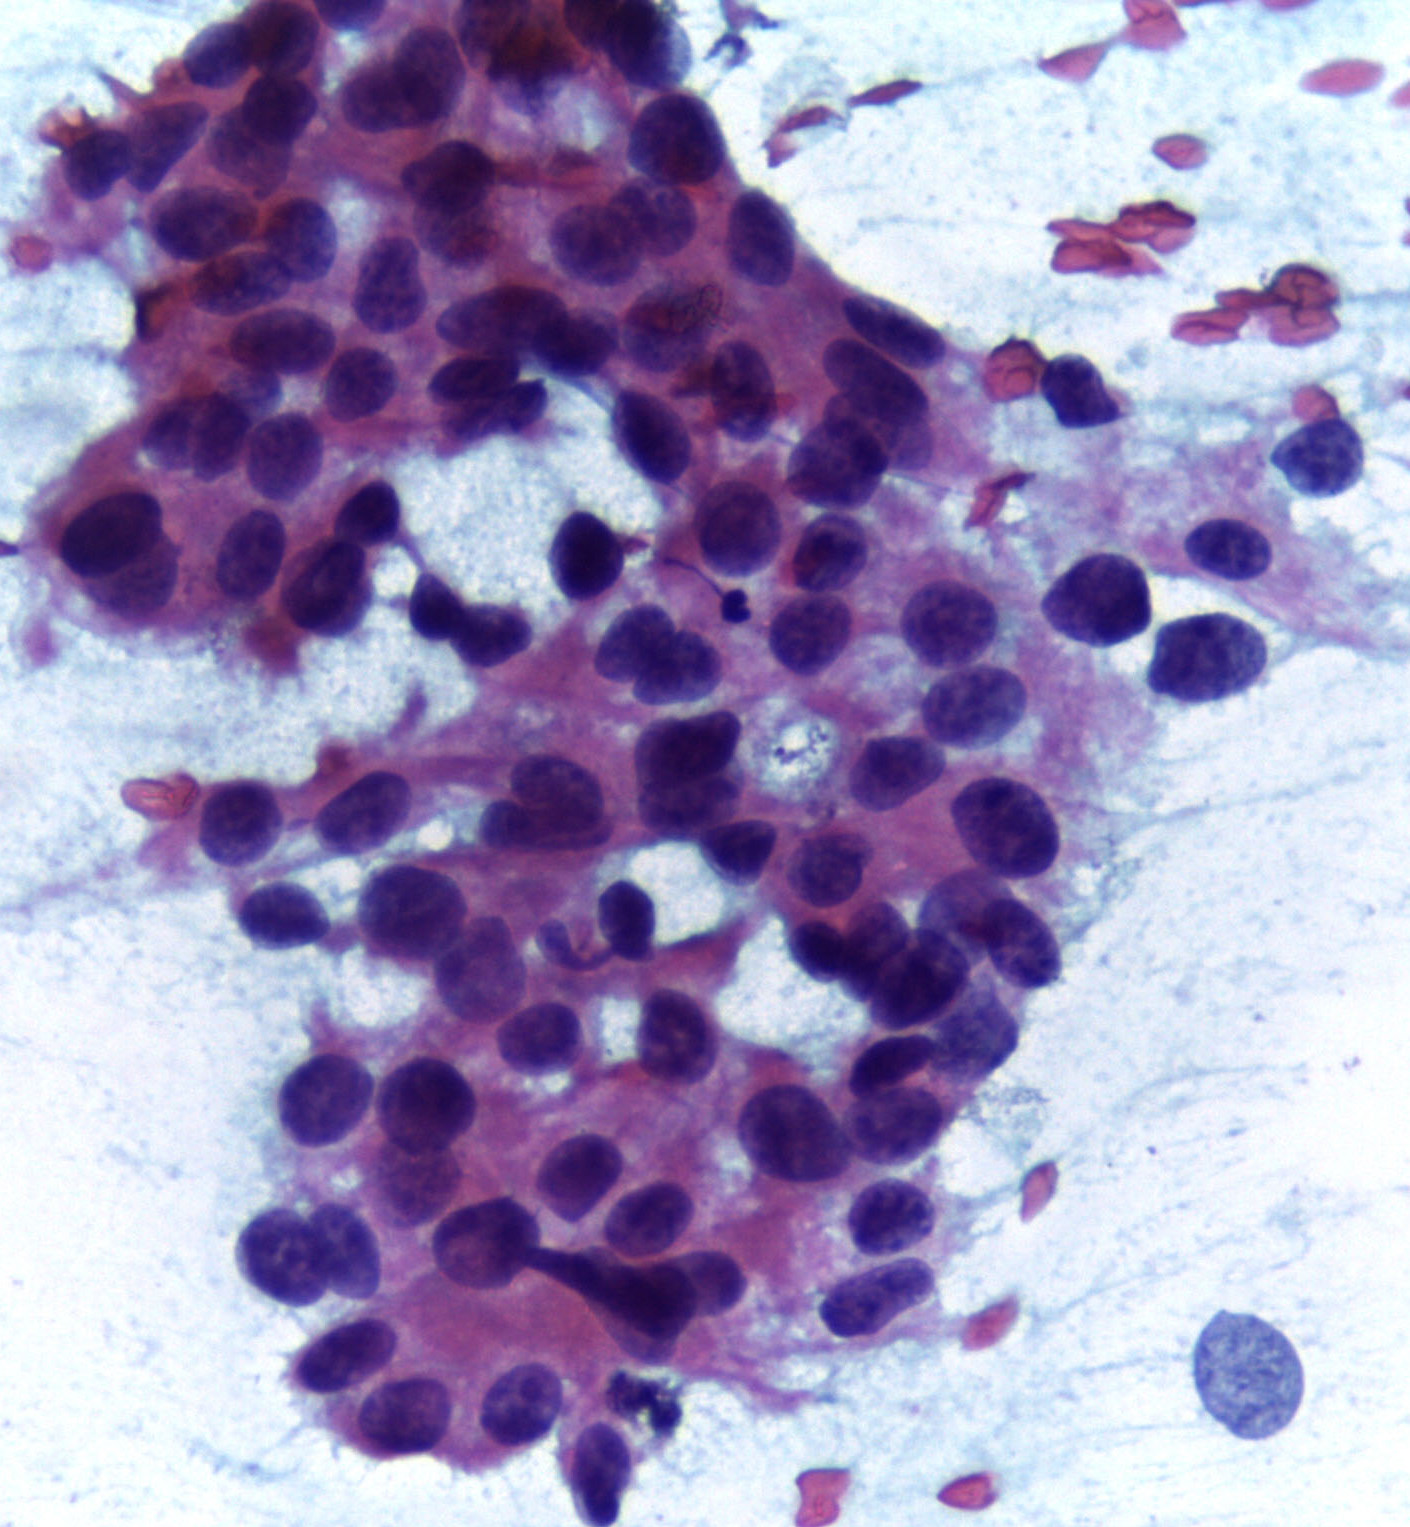

- Xét nghiệm tế bào bằng kim nhỏ (FNA): khi phát hiện tổn thương nghi ngờ, bệnh nhân có thể được chỉ định làm xét nghiệm tế bào học. Bác sĩ chuyên khoa Giải phẫu bệnh - tế bào sẽ sử dụng một chiếc kim vô trùng, tiếp cận tổn thương và thu thập mẫu bệnh phẩm, bệnh phẩm này được phân tích trên kính hiển vi để tìm kiếm tế bào ung thư.

Hình minh họa: tổn thương ung thư vú phát hiện trên xét nghiệm tế bào học

(Nguồn: commons.wikipedia.org)